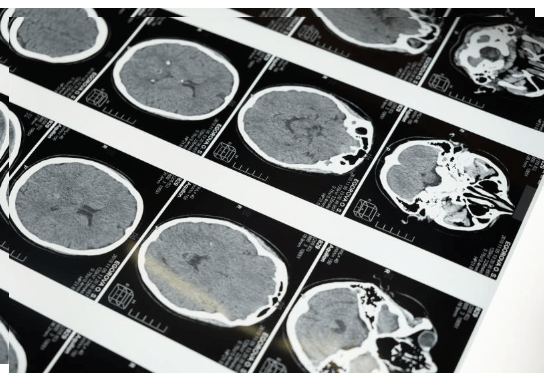

이런 사람들은 앞으로 아파도 건강보험 적용 받지 못하기 때문에 본인이 모든 병원비 부담해야 합니다.병원에서 수술 앞두고 보다 정밀한 검사 받기위해 꼭 한번쯤 시행하게 되는 검사로 초음파, CT, MRI 등 검사가 있습니다.

검사비용 병원마다 조금씩 다르지만,아무래도 동네 의원급 1차 병원에서 검사하는 비용보다 3차 대학병원을 통해 하는 검사 비용 더 높습니다.뇌 MRI 기준으로 병원급 이상 의료기관의 경우 최소 25만원 부터 최대 88만원 까지 다양한 검사비 청구됩니다.

10월부터 건강보험 적용이 달라진다는 내용은 바로 누구나 한번쯤 느낄 수 있는 두통,어지럼증 관련된 것으로,살면서 머리 아프고 불편하다고 한번쯤 느낄 때가 있습니다.지금까지 단순 두통,어지럼증 있을 경우 MRI 검사 받으면 건강보험 적용됨에 따라 비용에 대한 부담 조금은 덜 수 있었습니다.

하지만 앞으로는 단순 두통이나 어지럼으로 뇌 MRI 찰영할 경우 건강보험 적용 받지 못합니다.이는 뇌질환과 무관한 두통,어지럼증에 MRI 검사 비용 남용되는 것을 방지하기 위해 급여기준 구체화 한 것으로 의료진이 뇌출혈,뇌경색 등 뇌질환 의심되어 의학적으로 MRI검사 필요하다고 판단하여 촬영하는 경우에만 건강보험 적용 받을 수 있습니다.

즉, 환자는 두통이나 어지럼으로 뇌 MRI촬영 원하지만,의료진이 MRI검사 필요성 낮다고 판단하는 경우 환자가 원해서 촬영 진행한다면 건강보험 적용 받지 못한다는 것입니다.하지만 기존에 뇌질환 있었거나 신경학적 검사 등에서 이상 소견 있을 경우 이전과 같이 MRI검사 시 건강보험 적용된다고 하니 이 부분 함께 참고하면 좋겠습니다.